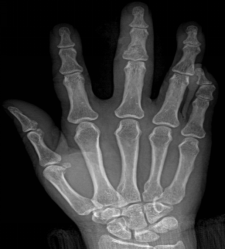

手骨

包括腕骨、掌骨、指 骨

腕骨共8块,近侧由桡侧向尺侧为:手舟骨、月骨、三角骨和

豆骨,远侧列为:大多角骨、小多角骨、头状骨和钩骨

8块腕骨构成一掌面凹陷的腕骨沟

掌骨共5块,近端为底,接腕骨;远端为头,接指骨;中间部为体

指骨共14块,拇指有2节,分为近节和远节指骨,其余各指为3节, 分为近节指骨,中节指骨和远节指骨。每节指骨近端为底,中间部为体,远端为滑车